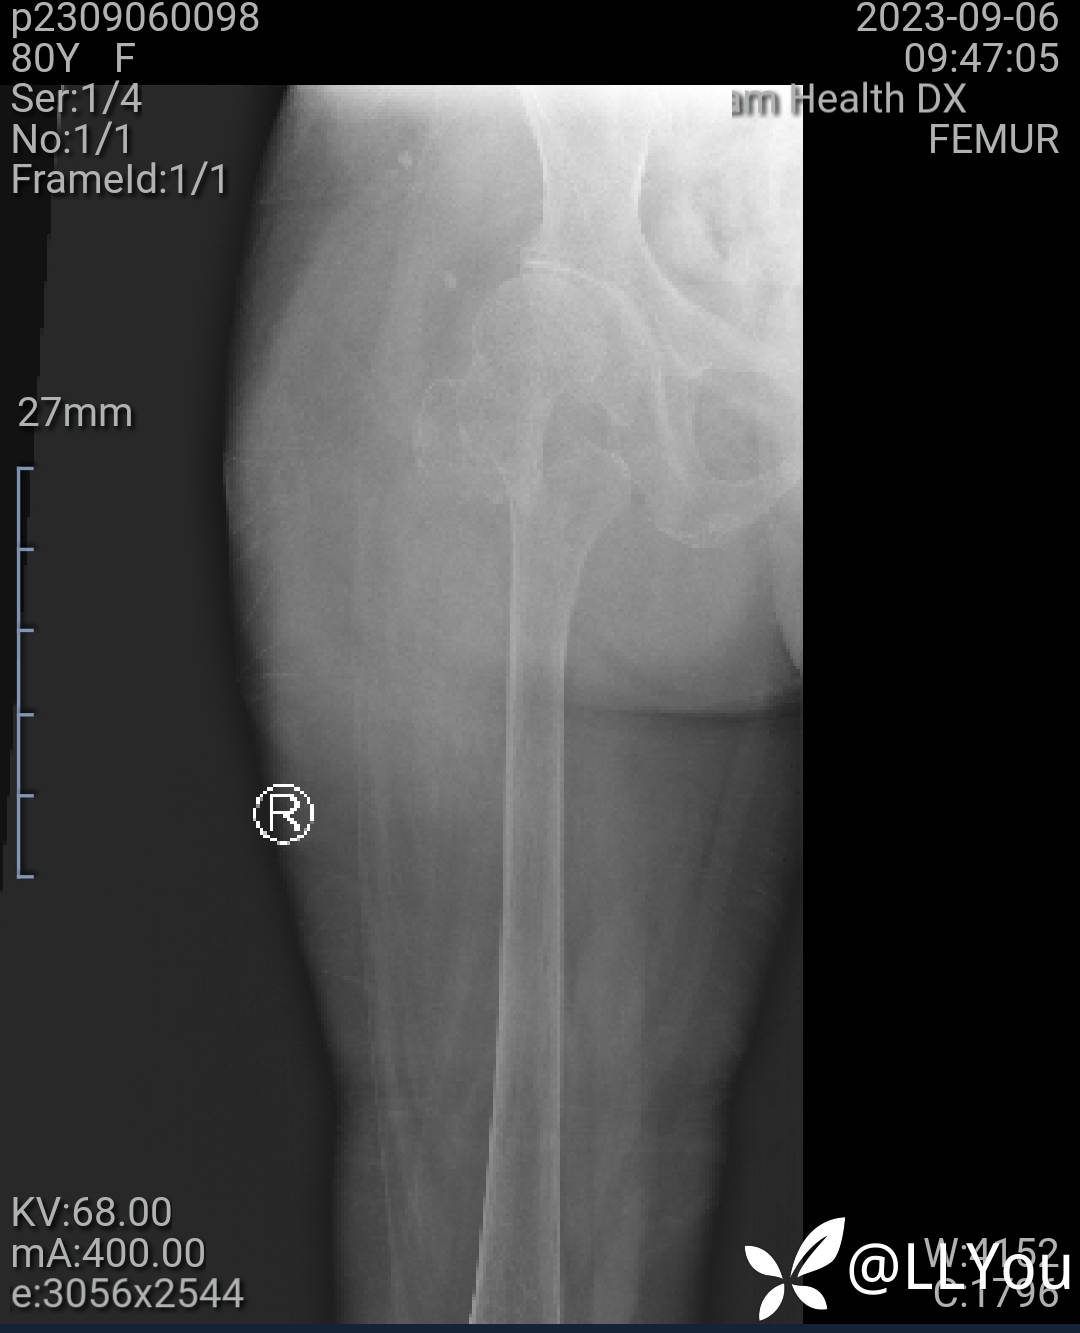

病人,女,80岁

既往高血压史

摔伤后髋关节疼痛功障碍来诊

查体:一般情况好,髋外旋畸形、功能障碍,未稍血运感觉正常。

拍X片见下图